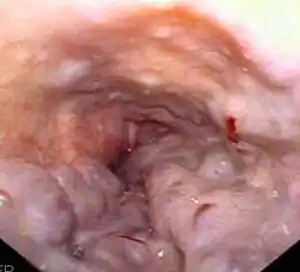

Gastroscopy image of esophageal varices with prominent cherry-red spots